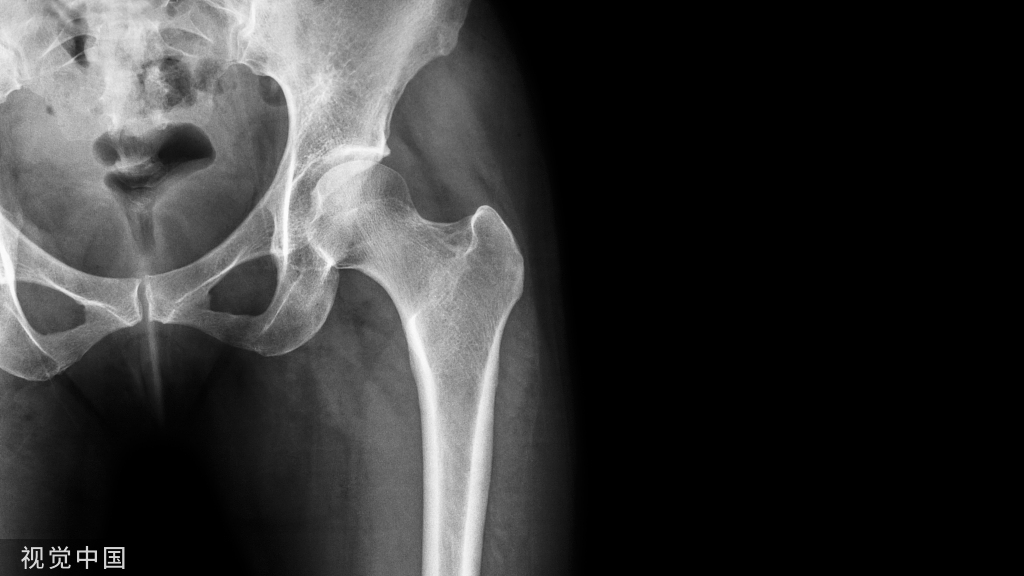

术前X线片:股骨远端骨不连,接骨板疲劳折断